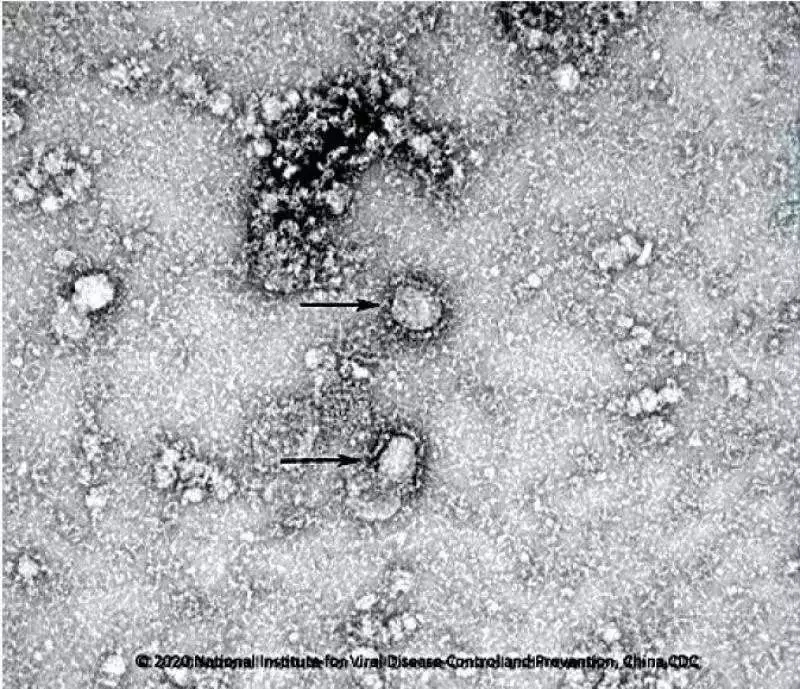

好消息!中國(guó)疾控中心成功分離我國(guó)首株新型冠狀病毒毒種

國(guó)家病原微生物資源庫(kù)于2020年1月24日發(fā)布了由中國(guó)疾病預(yù)防控制中心病毒病預(yù)防控制所成功分離的我國(guó)第一株病毒毒種信息及其電鏡照片、新型冠狀病毒核酸檢測(cè)引物和探針序列等國(guó)內(nèi)首次發(fā)布的重要權(quán)威信息,并提供共享服務(wù),鏈接:http://nmdc.cn/#/nCoV。戳圖看病毒“真容”。